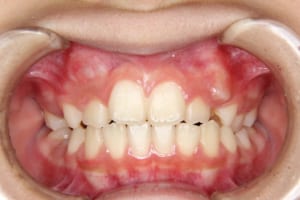

治療中